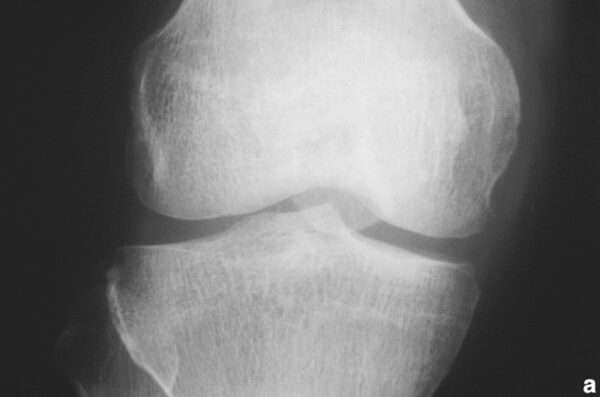

El reumatismo palindrómico es una enfermedad de causa desconocida, caracterizada por ataques recurrentes y frecuentes de inflamación articular aguda que ocurren a intervalos irregulares. Estos episodios se manifiestan con dolor…